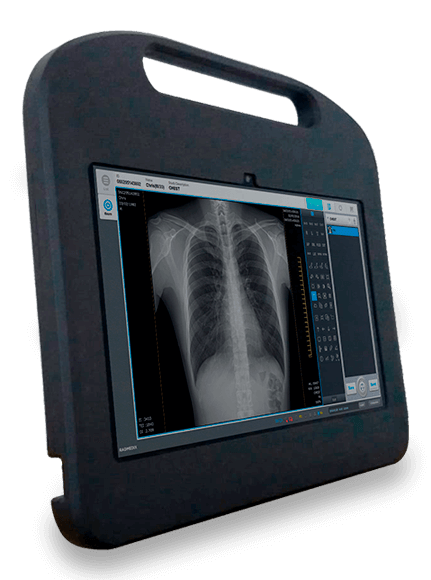

SISTEMA DE ADQUISICIÓN DE IMÁGENES

Práctico, cómodo e infaltable.

PC PORTATIL

Perfecta Compañía Para Tu Detector

Potente PC protegida por una carcasa rígida y resistente, pantalla táctil, doble wifi, acompañada por la última versión del software de adquisicion EConsole1.

- Amplia variedad, para todas las prácticas.

- Repertorio completo de herramientas.

- La mejor calidad de imagen.